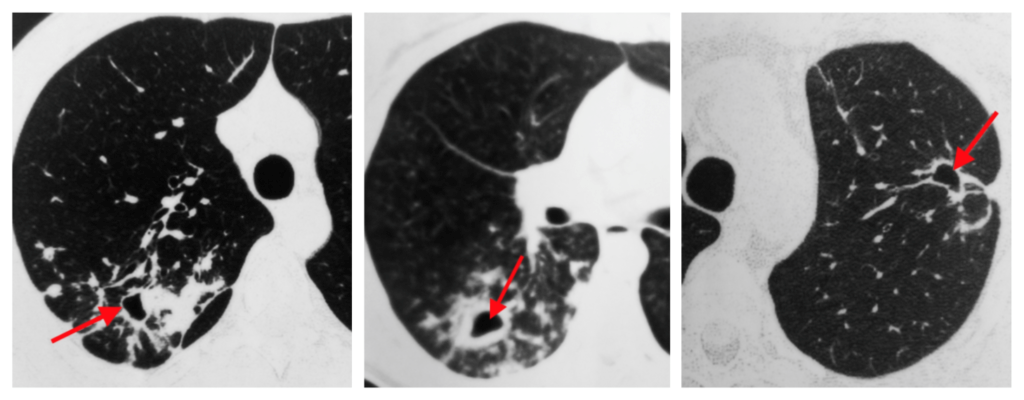

- Görüntüləmə əlamətlərinə rentgenoloji və KT müayinələrində ağciyərdə kütlə (kütlələr), bronxoskopiyada bronxial kütlənin görünməsini, USM və KT-də qaraciyərdə, sümüklərdə, böyrəküstü vəzidə və beyində kütlələrin tapılmasını aid etmək olar.

- Mediastinal strukturlara yayılmanı dəqiqləşdirmək üçün KT və endobronxial USM ilk seçimdir (Şəkil 11).

Şəkil 11. Ağciyər xərçənginin diaqnostikası (KT).